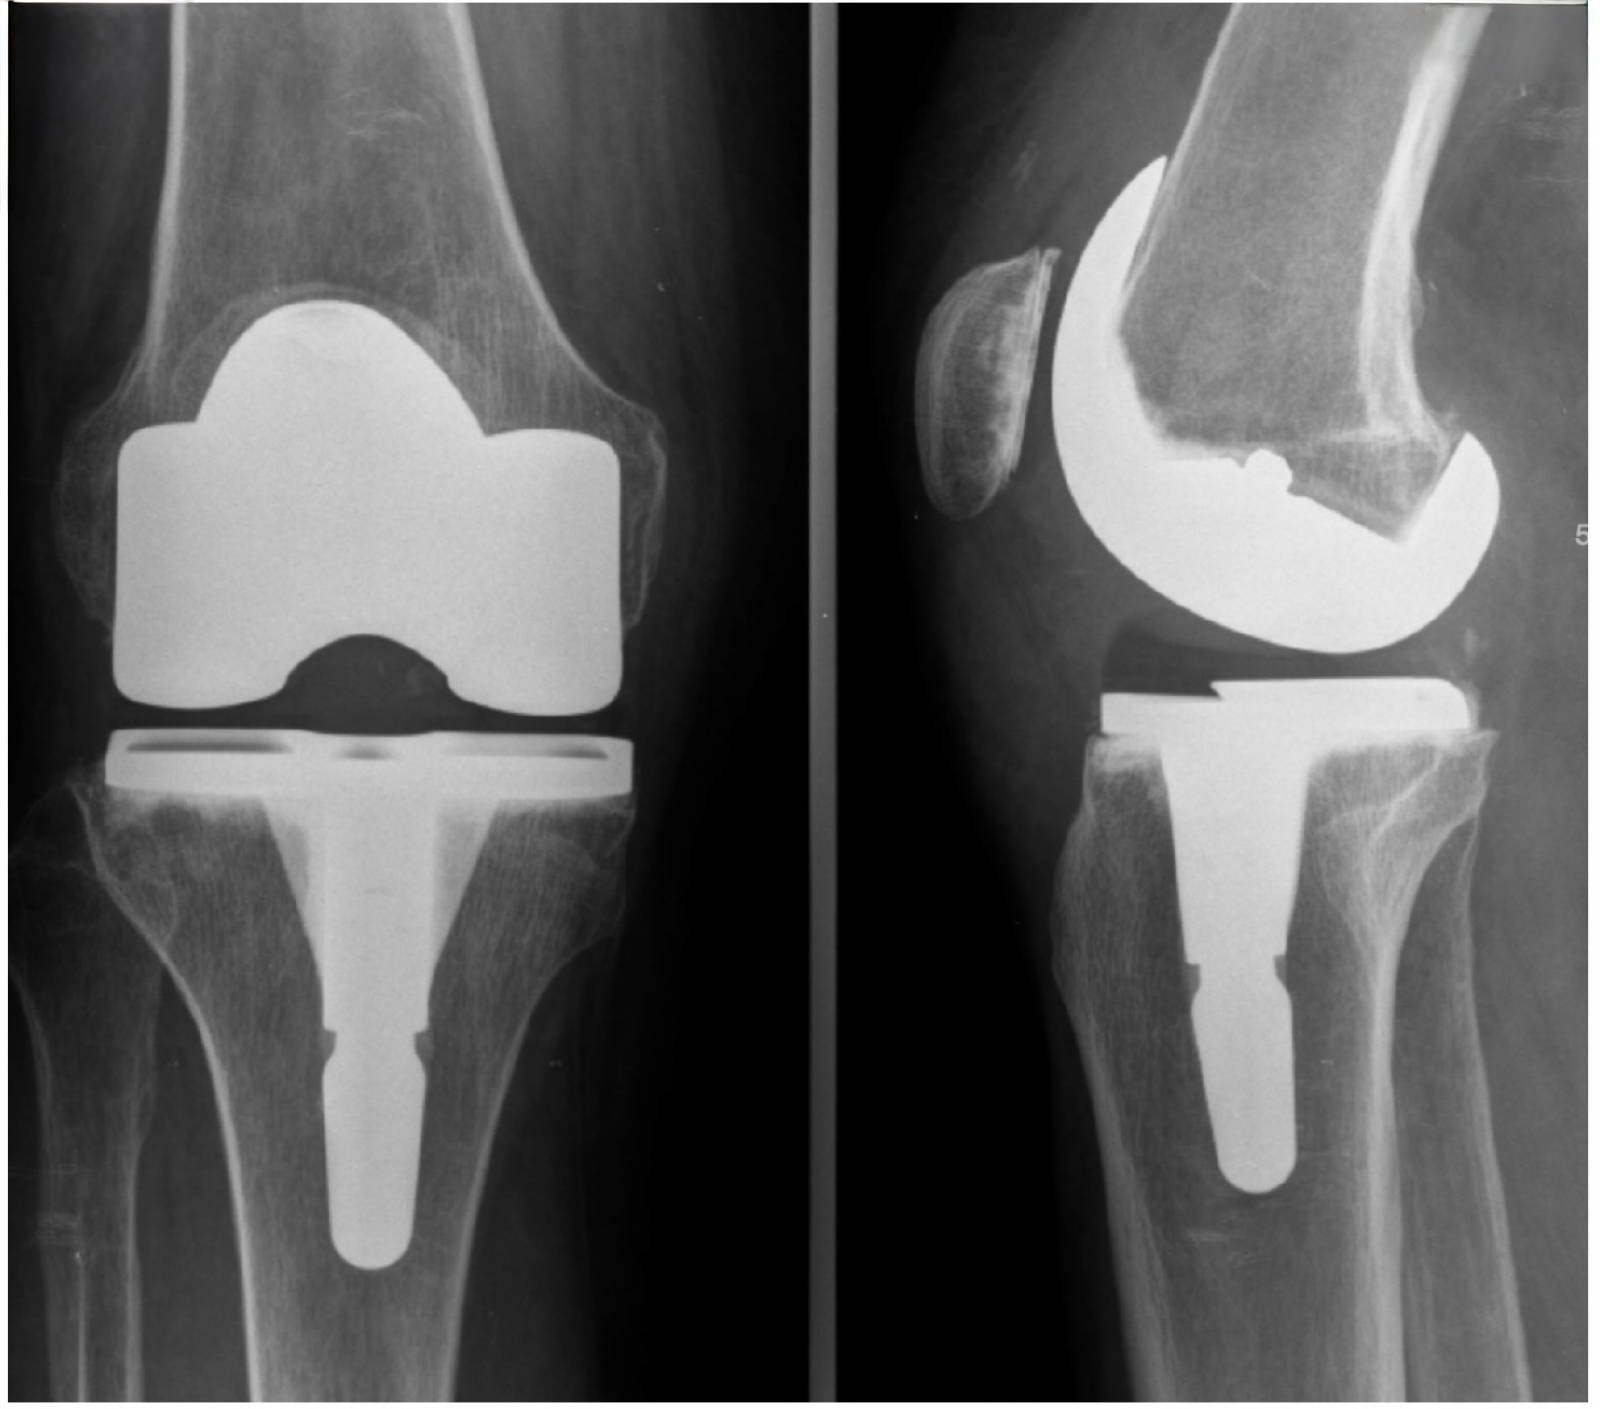

Prothèse totale du genou

La prothèse totale du genou remplace une articulation usée par l’arthrose.

Douleurs importantes, gêne fonctionnelle sévère malgré les traitements médicaux.

Diminution nette de la douleur et amélioration de la mobilité.

Rééducation indispensable, récupération progressive sur plusieurs semaines.